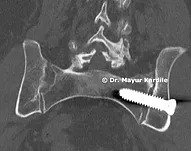

The Minimally Invasive Procedure

• Small 1-inch incision over the buttock • Three triangular titanium implants placed across the SI joint using image guidance • No large incision or muscle disruption • Procedure duration: 30–45 minutes • Patient walks same day • Discharge: Same day or next day